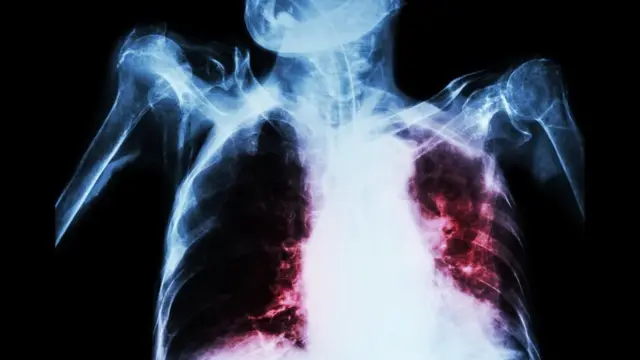

పంకజ్ ఊపిరితిత్తులను టీబీ దెబ్బతీసింది. ఆరు నెలల చికిత్స తరువాత ఆయన 80 శాతం కోలుకున్నారు. అయితే అసలు ఇబ్బందులు తరువాత వచ్చాయి.

ఆరు నెలల తరువాత ఫిబ్రవరిలో జరిపిన పరీక్షల్లో టీబీ బ్యాక్టీరియా ఆయన మెదడుకు కూడా పాకినట్టు తెలిసింది. మరో మూడు నెలలకు కంటి చూపు మందగించింది. తరువాత కాళ్లు చచ్చుబడిపోయాయి.

సైలెంట్ కిల్లర్ ట్యూబర్క్యులోసిస్

ప్రపంచ ఆరోగ్య సంస్థ (డబ్ల్యూహెచ్ఓ) గణాంకాల ప్రకారం ప్రపంచంలో మూడొంతుల మంది క్షయ వ్యాధిగ్రస్తులు భారతదేశంలోనే ఉన్నారు.

టీబీ కారణంగా ఇండియాలో ఏటా 4,80,000 మరణాలు సంభవిస్తున్నాయి.

భారత ప్రభుత్వ గణాంకాల ప్రకారం క్షయ కారణంగా దేశంలో రోజుకి 1,300 మంది చనిపోతున్నారు.

గత 50 ఏళ్లుగా టీబీని నివారించేందుకు ఇండియా పోరాటం చేస్తున్నప్పటికీ అది అంతం కావడం లేదు. అందుకే ఇప్పటికీ దీన్ని ‘సైలెంట్ కిల్లర్’ అని పిలుస్తున్నారు.